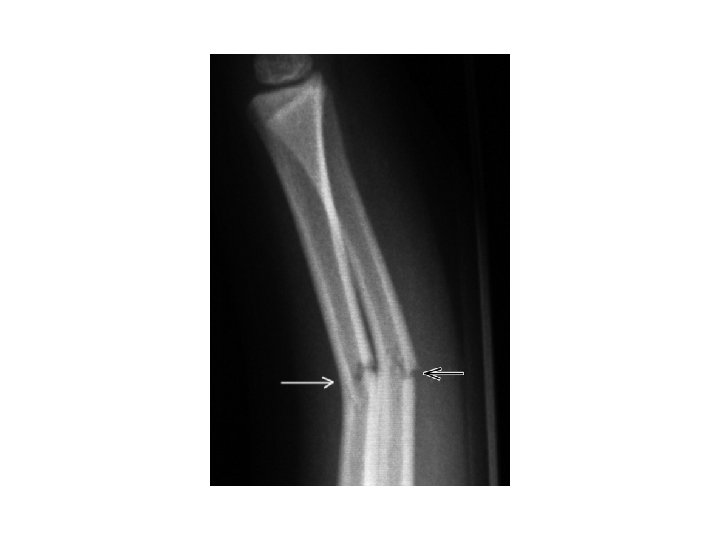

6. Question Identify the specific type of fracture in given X-ray.

Answer Green Stick Fracture Question Board